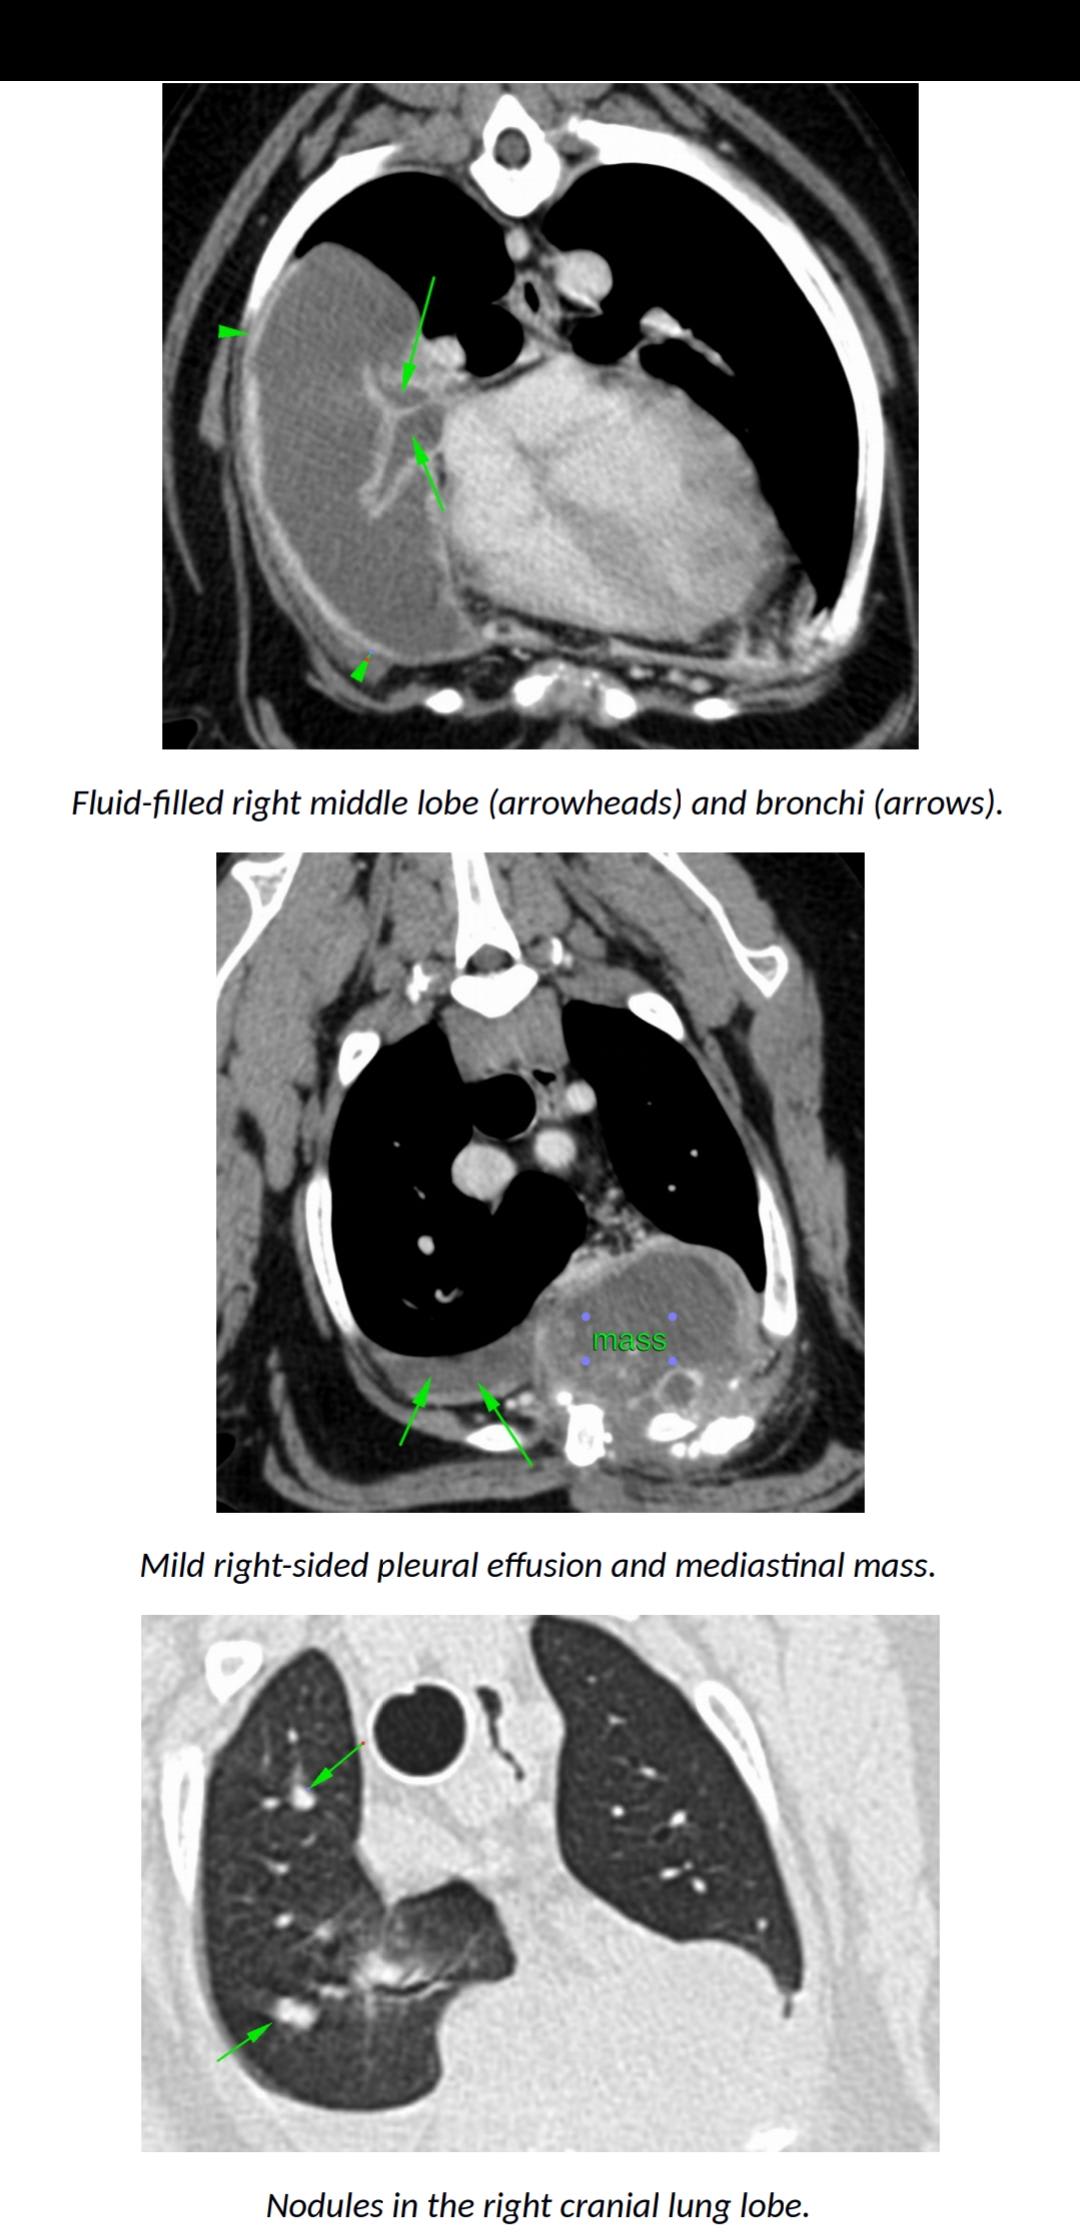

I'm sorry Yogi has a mass! From the images you provided, it looks like he has a mass in his mediastinum that has spread into his pectoral muscles, fluid in his right lung, and nodules in the right lung. I would be suspicious that the nodles in his right lung are cancer that has spread from the medilstinal mass. Dogs can have tumors and still appear normal, and then suddenly appear sick. Without seeing him in person I can't say for certain, but these images do not suggest good news for him. I certainly understand your concern about going on holiday and him going downhill while you aren't there. Speak with your vet to get their opinion on how long he may have left. You can decide to not go on your holiday to spend time with him, or you can go on the holiday, but leave him with a trusted friend and plan to head back home right away if things look poorly for him. It's a very hard decision to make, and I'm so sorry you are in this position. First speak with his vet to get a better idea of what he is facing so that you can make a more informed decision. Best of luck, I hope this helps.